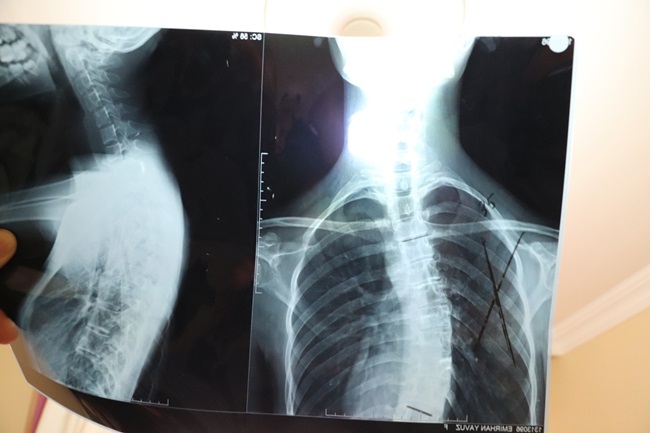

Zonguldak’ın Ereğli ilçesinde yaşayan 19 yaşındaki Otizmli Emirhan Yavuz, skolyoz hastalığı ameliyat edilemediği takdirde hayatını kaybetmekle karşı karşıya. Anne Eda Tok, tek başına bakmaya çalıştığı oğlunu kurtarmak için hayırseverlerden yardım bekliyor.

Kısa süreye kadar İstanbul’da yaşayan ve eşinden boşanması üzerine memleketi Ereğli’ye yerleşen Eda Tok, otizmli olan 19 yaşında ki skolyoz rahatsızlığı oğlunu tedavi ettirmek için yardım bekliyor. Bugüne kadar birçok Devlet Hastanesine giden ancak burada oğlunun ameliyatı için çözüm arayan anne Eda Tok, gittiği her hastaneden eli boş döndüğünü söyledi. Özel hastanelere de gittiğini ancak özel hastanelerde de yaklaşık 50 bin liralık bir maliyet kendisine çıkarıldığını kaydeden anne Eda Tok, imkânsızlıklardan dolayı ameliyatı gerçekleştiremediklerini kaydetti.

Skolyoz hastalığından dolayı iç organların da zarar görmeye başladığını ve kısa zaman da ameliyat olmaması durumunda oğlunun hayatını kaybedeceğini ifade eden anne Eda Tok “Çocuğum Otizm hastası. 10 yaşından bu yana çekiyoruz. İstanbul ilinde birçok hastanede gösterdik. Ama ameliyat olmayacağını söylediler. Ailevi nedenlerden dolayı Ereğli’ye geldik. Buradaki hastanelere de gittik. Onlarda aynı cevabı verdiler. Özel hastaneye gönderdiler. Özel hastanelerde de maddi durumdan dolayı ameliyat yaptıramadık. Doktorlar bir an önce ameliyat olmazsa oğlumun hayatını kaybedeceğini söylediler. Ben yardımseverlerden devlet büyüklerimden bana destek vermelerini ve yardım etmelerini istiyorum. Oğlumu kaybetmek istemiyorum” dedi.